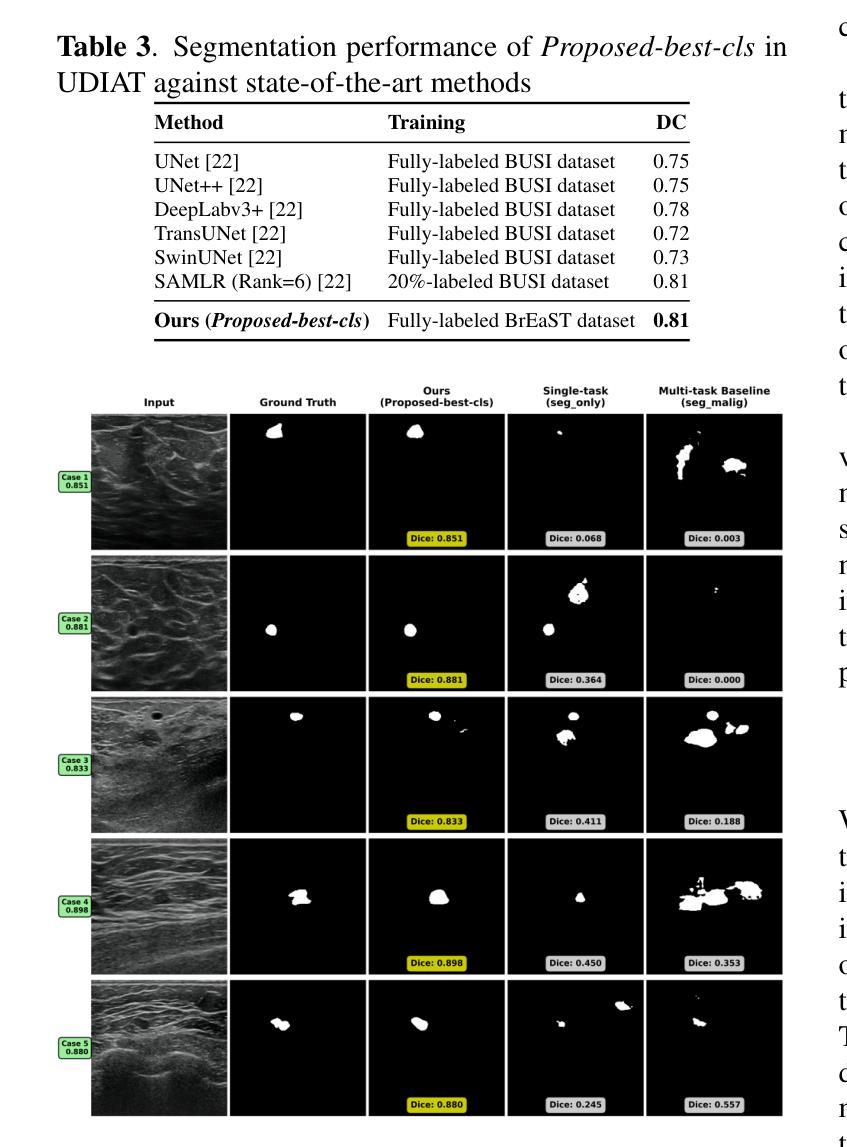

Externally Validated Multi-Task Learning via Consistency Regularization Using Differentiable BI-RADS Features for Breast Ultrasound Tumor Segmentation

Authors:Jingru Zhang, Saed Moradi, Ashirbani Saha

Multi-task learning can suffer from destructive task interference, where jointly trained models underperform single-task baselines and limit generalization. To improve generalization performance in breast ultrasound-based tumor segmentation via multi-task learning, we propose a novel consistency regularization approach that mitigates destructive interference between segmentation and classification. The consistency regularization approach is composed of differentiable BI-RADS-inspired morphological features. We validated this approach by training all models on the BrEaST dataset (Poland) and evaluating them on three external datasets: UDIAT (Spain), BUSI (Egypt), and BUS-UCLM (Spain). Our comprehensive analysis demonstrates statistically significant (p<0.001) improvements in generalization for segmentation task of the proposed multi-task approach vs. the baseline one: UDIAT, BUSI, BUS-UCLM (Dice coefficient=0.81 vs 0.59, 0.66 vs 0.56, 0.69 vs 0.49, resp.). The proposed approach also achieves state-of-the-art segmentation performance under rigorous external validation on the UDIAT dataset.

多任务学习可能会受到破坏性任务干扰的影响,联合训练的模型在单任务基准测试中的表现较差,并限制了模型的泛化能力。为了改善基于乳腺超声的肿瘤分割中多任务学习的泛化性能,我们提出了一种新的一致性正则化方法,该方法减轻了分割和分类之间的破坏性干扰。一致性正则化方法由可启发的BI-RADS形态特征组成。我们通过使用波兰的BrEaST数据集进行模型训练,并在三个外部数据集(UDIAT(西班牙)、BUSI(埃及)和BUS-UCLM(西班牙))上评估模型的有效性来验证了该方法。我们的综合分析表明,与基线相比,所提出的多任务方法在泛化方面具有统计学上的显著差异(p<0.001):在UDIAT、BUSI和BUS-UCLM数据集上,Dice系数分别为0.81 vs 0.59、0.66 vs 0.56、以及0.69 vs 0.49。此外,在UDIAT数据集上严格进行外部验证时,所提出的方法也达到了最先进的分割性能。

Summary

多任务学习可能导致破坏性任务干扰,影响联合训练模型的性能并限制其泛化能力。为改善基于乳腺超声的肿瘤分割的泛化性能,我们提出了一种新型一致性正则化方法,该方法可缓解分割与分类之间的破坏性干扰。一致性正则化方法由可借鉴的BI-RADS启发形态特征构成。我们在BrEaST数据集(波兰)上训练所有模型,并在三个外部数据集:UDIAT(西班牙)、BUSI(埃及)和BUS-UCLM(西班牙)上进行评估。综合分析显示,所提出的多任务方法在泛化方面相较于基线方法有显著改进(p<0.001):UDIAT、BUSI、BUS-UCLM的Dice系数分别为0.81 vs 0.59、0.66 vs 0.56、0.69 vs 0.49。此外,该方法在UDIAT数据集上实现了先进的分割性能。